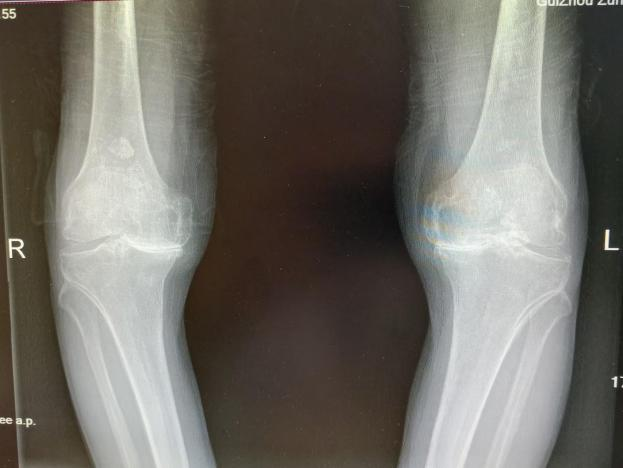

4月23日,贵州航天医院第58次晨读会由我院骨科副主任医师张艳金作学术交流,他以“加速康复指导下的快速手术”为题,详细讲解了老年股骨粗隆间骨折与儿童四肢骨折的临床诊疗难点,结合加速康复外科(ERAS)核心理念,重点阐述了ERAS理念在两大人群中的创新实践,实现患者入院后6至24小时内即可接受手术治疗。针对老年髋部骨折患者,提出通过多学科协作(MDT)与微创手术优化围术期管理,在确保安全前提下缩短术前等待时间,实施精准化麻醉及术后康复方案,可有效降低并发症发生率、改善患者生活质量和预后效果。在儿童骨折领域,强调微创术式与心理干预并行的双轨策略,既减少手术创伤对骨骼发育的影响,同时关注患儿心理疏导,实现生理功能与心理健康同步康复。并通过典型案例的影像学资料与随访数据,直观展示了ERAS理念指导下骨科治疗模式的创新成果。 贵州航天医院骨科 专家简介 赵学平 中共党员,骨科党支部书记、主任,主任医师 临床擅长:从事骨科临床工作30余年,对骨科常见疾病的诊治具有丰富的临床经验。 世界中医药联合会脊柱康复专业委员会常务理事,中华中医药学会整脊分会常务委员,中国中西医结合学会骨伤科分会肢体矫形功能重建与康复专家委员会常务委员,中国研究性医院学会骨科创新与转换专业委员会关节外科学组保髋工作委员会常委,中国康复技术转化及发展促进会骨外科与康复技术转化专业委员会常务委员,泛珠三角区域运动医学联盟(PPRD-SMA)理事会常务理事,中国研究型医院学会运动医学专业委员会委员,贵州省中医药学会整脊分会副主任委员,贵州省中西医结合学会银质针专业委员会副主任委员,贵州省康复医学会骨与关节专业委员会常务委员,贵州省人民医院骨科专科联盟常务理事,贵州省康复医学会骨内科专业委员会常务委员,中华医学会贵州省骨科学会委员,贵州省康复医学会脊柱脊髓专业委员会常务委员,贵州省运动医学分会委员,贵州省康复医学会骨与软组织肿瘤专业委员会委员,遵义市医学会创伤分会副主任委员,贵州省康复医学会骨内科专业委员会遵义地区分会常务委员,遵义市医疗事故鉴定、伤残鉴定、工伤鉴定、司法鉴定专家。 长期从事骨科临床研究及教学工作,在国家级、省部级杂志发表论文20余篇,SCI论文2篇,参与主编骨科专著2部,主持省部级科研项目2项,参与指导省部级、市级科研项目6项。 陈明勇 骨科副主任,副主任医师 临床擅长:从事创伤骨科工作约20年,对骨缺损、骨不连、骨肿瘤、肢体畸形等的肢体矫形重建及功能重建,慢性化脓性骨髓炎的根治治疗、糖尿病足的保肢治疗、快速康复理念(ERAS)下的老年骨折的诊治,四肢复杂骨折的诊治,四肢骨折等微创手术治疗具有丰富的临床经验。 2004年毕业于遵义医学院临床专业,曾在中国人民解放军总医院、广西医科大学第一附属医院、上海第六人民医院骨科进修。中国中西医结合学会骨伤科专业委员会横向骨搬移治疗糖尿病足及微血管网再生学组首届委员,遵义市医学会创伤分会常务委员。 瞿 辉 中共党员,骨科副主任医师 临床擅长:对骨科的常见病、关节外科、脊柱外科及运动医学疾病的诊治具有丰富的临床经验,熟练掌握骨科手术操作技术。 毕业于遵义医学院临床医学系,2005年前往广州中山大学第一附院骨显微医学部进修学习,2011年前往成都华西医院进修学习,并多次在省内外学习骨科相关知识,是中华医学会骨科分会会员。 赵兴东 骨科主任医师 临床擅长:擅长骨科的常见病及各种创伤、四肢骨折创伤修复、骨感染、手足疾病的诊治和手足体表畸形的矫形整复,熟练掌握骨科四肢骨病及创伤的手术操作技术,尤其在四肢关节复杂性损伤、手足外伤、组织缺损创面、难治创面的皮瓣修复方面及平足、高弓足矫形方面及四肢慢性疼痛诊治、康复方面具有丰富的临床经验。 硕士研究生,毕业于遵义医学院临床外科系,2015年前往山东省立医院手足外科进修学习;遵义市医学分会创伤分会第一、二届委员,遵义市手外科医学会第二委届员会常务委员;在省级及省级以上期刊发表文章9篇,参编著作2部,参与主持并完成市级课题1项,参与市级课题2项、省级课题1项。 张艳金 中共党员,骨科副主任医师 临床擅长:从事骨外科工作16年,对复合伤、多发伤的救治、四肢骨干骨折、关节周围骨折、骨肿瘤、骨髓炎等诊治具有丰富的临床经验。 中共党员,硕士研究生,2006年本科毕业于山西医科大学第二临床医学院,2011年研究生毕业于北京军区总医院;在“老年COPD患者合并髋部骨折的诊治”国际合作课题组研究两年,在老年髋部骨折的诊治方面具有丰富的经验,并发表论文6篇;主持遵义市级课题1项,承担遵义医科大学的临床教学工作,获得遵义医科大学优秀带教老师荣誉。编撰有《骨科疾病诊疗精粹》一书,开展2项新技术,编撰地方规范《务川自治县创伤骨科常见疾病诊疗规范》一书。 张俊凯 骨科副主任医师 临床擅长:从事骨科临床工作28年,对创伤骨折、骨感染、骨缺损、骨不连等外科诊治,四肢骨折的微创手术治疗,四肢复杂骨折(如关节内粉碎性骨折、多发骨折等)的损伤控制及手术治疗等具有丰富的临床经验。 1995年毕业于遵义医学院临床专业,2009年前往复旦大学附属医院骨科进修1年。 卢懿明 中共党员,骨科副主任医师 临床擅长:从事骨科工作18年,对创伤骨折、四肢骨折的微创手术治疗、四肢复杂骨折(如关节内粉碎性骨折、多发骨折等)的损伤控制及手术治疗,尤其是髋部骨折的PFNA等微创技术,踝关节骨折、膝关节周围骨折的Mipo微创技术等具有丰富的临床经验,开展了4项新技术,发明6项新型专利技术。 2005年毕业于遵义医学院临床专业,2017年,前往南方医科大学第三附属医院骨科进修半年,回院后运用Mipo技术对骨干骨折及干骺端骨折的治疗技术,同时积极开展骨盆骨折、髋臼骨折腹直肌外侧切口的应用;发表了多篇专业论文,经常参与省内外学术交流会授课,获得医院荣誉称号多个。 邬夏荣 骨科副主任医师 临床擅长:从事骨科工作16年,对四肢复杂骨折、骨肿瘤的诊治,尤其是足踝创伤、慢性踝关节损伤、平足症等诊疗具有丰富的临床经验。 2006年毕业于遵义医科大学临床医学专业,曾在陆军军医大学西南医院进修学习,发表多篇骨科学术论文。 余德怀 中共党员,骨科副主任医师 临床擅长:从事骨科工作10余年,对运动医学、骨关节、脊柱外科常见病、多发病的诊治具有丰富的临床经验。 硕士研究生,2011年毕业于遵义医学院临床医学专业,曾前往遵义医科大学附属医院运动医学专业进修学习;是贵州省医学会运动医学分会青年委员,西部关节镜联盟委员;发表多篇骨科学术论文。 冯 乾 骨科副主任医师 临床擅长:从事骨科工作近20年,熟练掌握骨科多发病及常见病的诊治,尤其对脊柱退变性疾病的诊断及治疗具有丰富的临床经验,主要研究脊柱微创相关治疗方式,能熟练开展椎间孔镜及UBE。 曾前往北京大学第三医院进修学习疼痛及椎间孔镜、首都医科大学友谊医院专业进修脊柱内镜;是贵州省康复医学会第三届脊柱脊髓专业委员会委员;发明专利3项、发表脊柱外科专业论文多篇。 赵小锋 中共党员,骨科副主任医师 临床擅长:从事骨科临床工作11年,对骨科常见病、多发病诊疗有较为丰富的临床经验,擅长脊柱相关疾病诊断及治疗,尤其是颈、腰、腿疼痛疾病诊断及治疗,擅长胸腰椎骨折微创经皮穿刺内固定术、经皮穿刺椎体成形术、经皮穿刺脊柱内镜下腰椎间盘摘除术、单纯开创腰椎间盘摘除术、腰椎滑脱复位椎间植骨椎融合内固定术、腰椎管狭窄减压融合内固定术及人工髋、膝关节置换术等。 2012年毕业于遵义医学院外科学专业硕士研究生,2019年参加“遵义市115医学人才精英计划”于上海交通大学第一附属医院培训学习,2023年于北京大学第三人民医院脊柱外科进修学习,曾获得遵义市优秀医师荣誉称号。 遵义市手外科第一届委员,遵义市医学会创伤分会第一届委员,遵义市医学会创伤分会第二届委员,贵州省康复医学会第三届脊柱脊髓专业会委员,遵义市医学会烧伤与整形外科学分会委员,发表论文5篇,其中国家级核心期刊1篇,SCI论文1篇,主持市级课题1项并结题,参与市级课题2项。 贵州航天医院骨科 简介 基本情况 贵州航天医院骨科组建于20世纪60年代,前身是以创伤和断肢(断指)再植闻名于世的上海市第六人民医院骨科,中国断肢(断指)再植的奠基者、中科院院士陈仲伟等著名专家、学者多次莅临科室指导医疗、教学,是贵州省最早拥有专业骨科技术科室之一,在70年代开展了贵州省首例断肢(断指)再植手术。组建50余年来,诊治患者已逾百万,挽救了无数的伤病员,成为了保障遵义地区人民群众健康的重要支撑。 经过几代人的不懈努力,今天的骨科,已由创伤骨科发展至骨病、骨肿瘤、骨结核等领域,现有脊柱外科、关节外科、四肢创伤、手足外科四个亚专科,成为了集医疗、教学、科研于一体的综合学科,是贵州省临床重点专科、遵义市临床重点专科、遵义市骨科临床医学中心、遵义市基层骨科专科联盟理事长单位。 科室目前开放床位110张,共有医护人员50余人,副高级以上专家18人,硕士研究生15人。拥有一流骨科医疗设备多台,每年不定期选派优秀技术骨干到全国各大知名医学院校进修、学习、参观、交流,并邀请国内、国外知名专家教授来院进行交流、指导,通过不断引进国内外先进的诊疗技术,科室医疗技术水平稳步提升,为广大人民群众提供了优质的医疗服务。 专科特色 骨一科 (一)骨缺损、骨不连的肢体与功能重建 胫骨横向骨搬移技术治疗糖尿病足: (二)慢性骨髓炎的根治治疗 (三)肢体缺血性疾病如糖尿病足、脉管炎的保肢治疗 (四)皮瓣修复 (五)复杂创伤的治疗 (六)老年髋部骨折及小儿骨折快速手术 老年髋部骨折: 骨二科 (一)胸腰椎骨折微创经皮椎弓根螺钉固定术 (二)老年性骨质疏松性患者腰椎滑脱脊柱内固定术(骨水泥螺钉) (三)V形双通道脊柱内镜技术(VBE)腰椎融合术治疗腰椎退行性疾病 (四)老年性骨质疏松性骨折(PVP/PKP)术 (五)人工髋关节置换术 (六)双侧股骨头坏死人工全髋关节置换 (七)右侧全髋置换术后假体周围骨折翻修 (八)人工膝关节置换术 (九)人工膝关节假体松动翻修 (十)关节镜技术 传统手术切口 关节镜技术切口 诊疗范围 骨一科 1.四肢创伤、矫形。 2.手、足踝外科。 骨二科 end